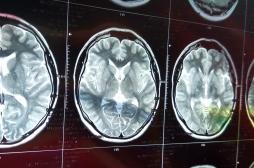

LES MALADIES